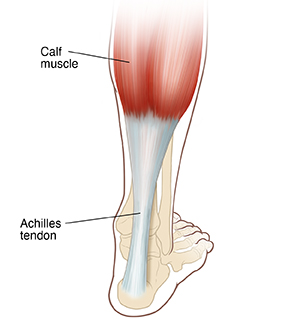

The Achilles tendon is a strong, fibrous cord in the back of your lower leg. It connects the calf muscles to your heel. It’s the largest tendon in your body. It helps you walk, run, and jump. Achilles tendon repair surgery is done to fix the damaged tendon.

Repair of an Achilles tendon is done by an orthopedic surgeon. This is a surgeon who treats bone, muscle, joint, and tendon problems. The surgery can be done in several ways. The surgeon will make a cut (incision) through the skin and muscle in the back of your calf. If you have minimally invasive surgery, the surgeon will make several smaller incisions instead of one large one. Your surgeon will make an incision through the sheath or covering of the Achilles tendon. If the tendon is damaged, the surgeon may remove the damaged part and repair the rest of it. If you have severe damage, the surgeon may use a muscle or tendon from your calf, ankle, or foot for the repair.